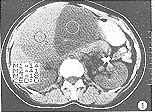

CT诊断肝脏囊腺瘤并囊内出血一例